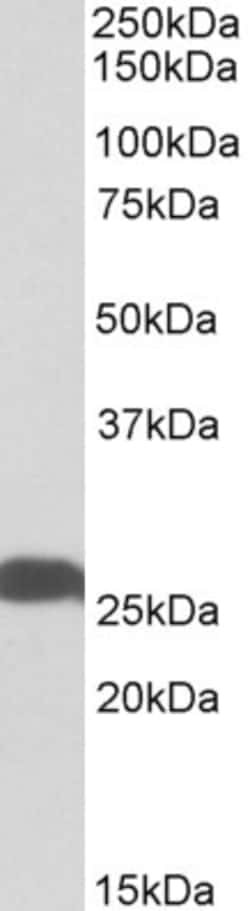

Invitrogen™ PGP9.5 Polyclonal Antibody

This antibody is predicted to react with bovine, canine and porcine based on sequence homology. This antibody has been successfully tested in a Sandwhich ELISA as both a capture and a detection antibody in combination with PA5-19350.

PGP9.5 (Protein gene product 9.5, UCH-L1, PARK5) is a neuron specific protein, structurally and immunologically distinct from neuron specific enolase. PGP9.5 has a molecular weight of 27 kDa and was first identified by high resolution two dimensional PAGE. PGP9.5 is a member of ubiquitin carboxyl-terminal hydrolase family 1 (peptidase family C12) with a ubiquitin carboxyl-terminal hydrolase domain. PGP9.5 is well known for having ubiquitin hydrolase and ligase activities that hydrolyzes small C-terminal adducts of ubiquitin to generate ubiquitin monomers. PGP9.5 is present in neurons and nerve fibers at all levels of the central and peripheral nervous system, in neuroendocrine cells, in segments of the renal tubules, in spermatogonia and Leydig cells of the testis, in ova and in some cells of both the pregnant and non-pregnant corpus luteum. Over expression of PGP9.5 leads to non-small cell lung cancer while decreased expression leads to Huntington disease and Alzheimer disease. Since PGP9.5 is present in cellular inclusions, it can be a useful as a neuronal marker and in the studies of neurodegenerative disorders such as with Parkinson disease.

| Immunohistochemistry (Paraffin), Western Blot, Western Blot | |